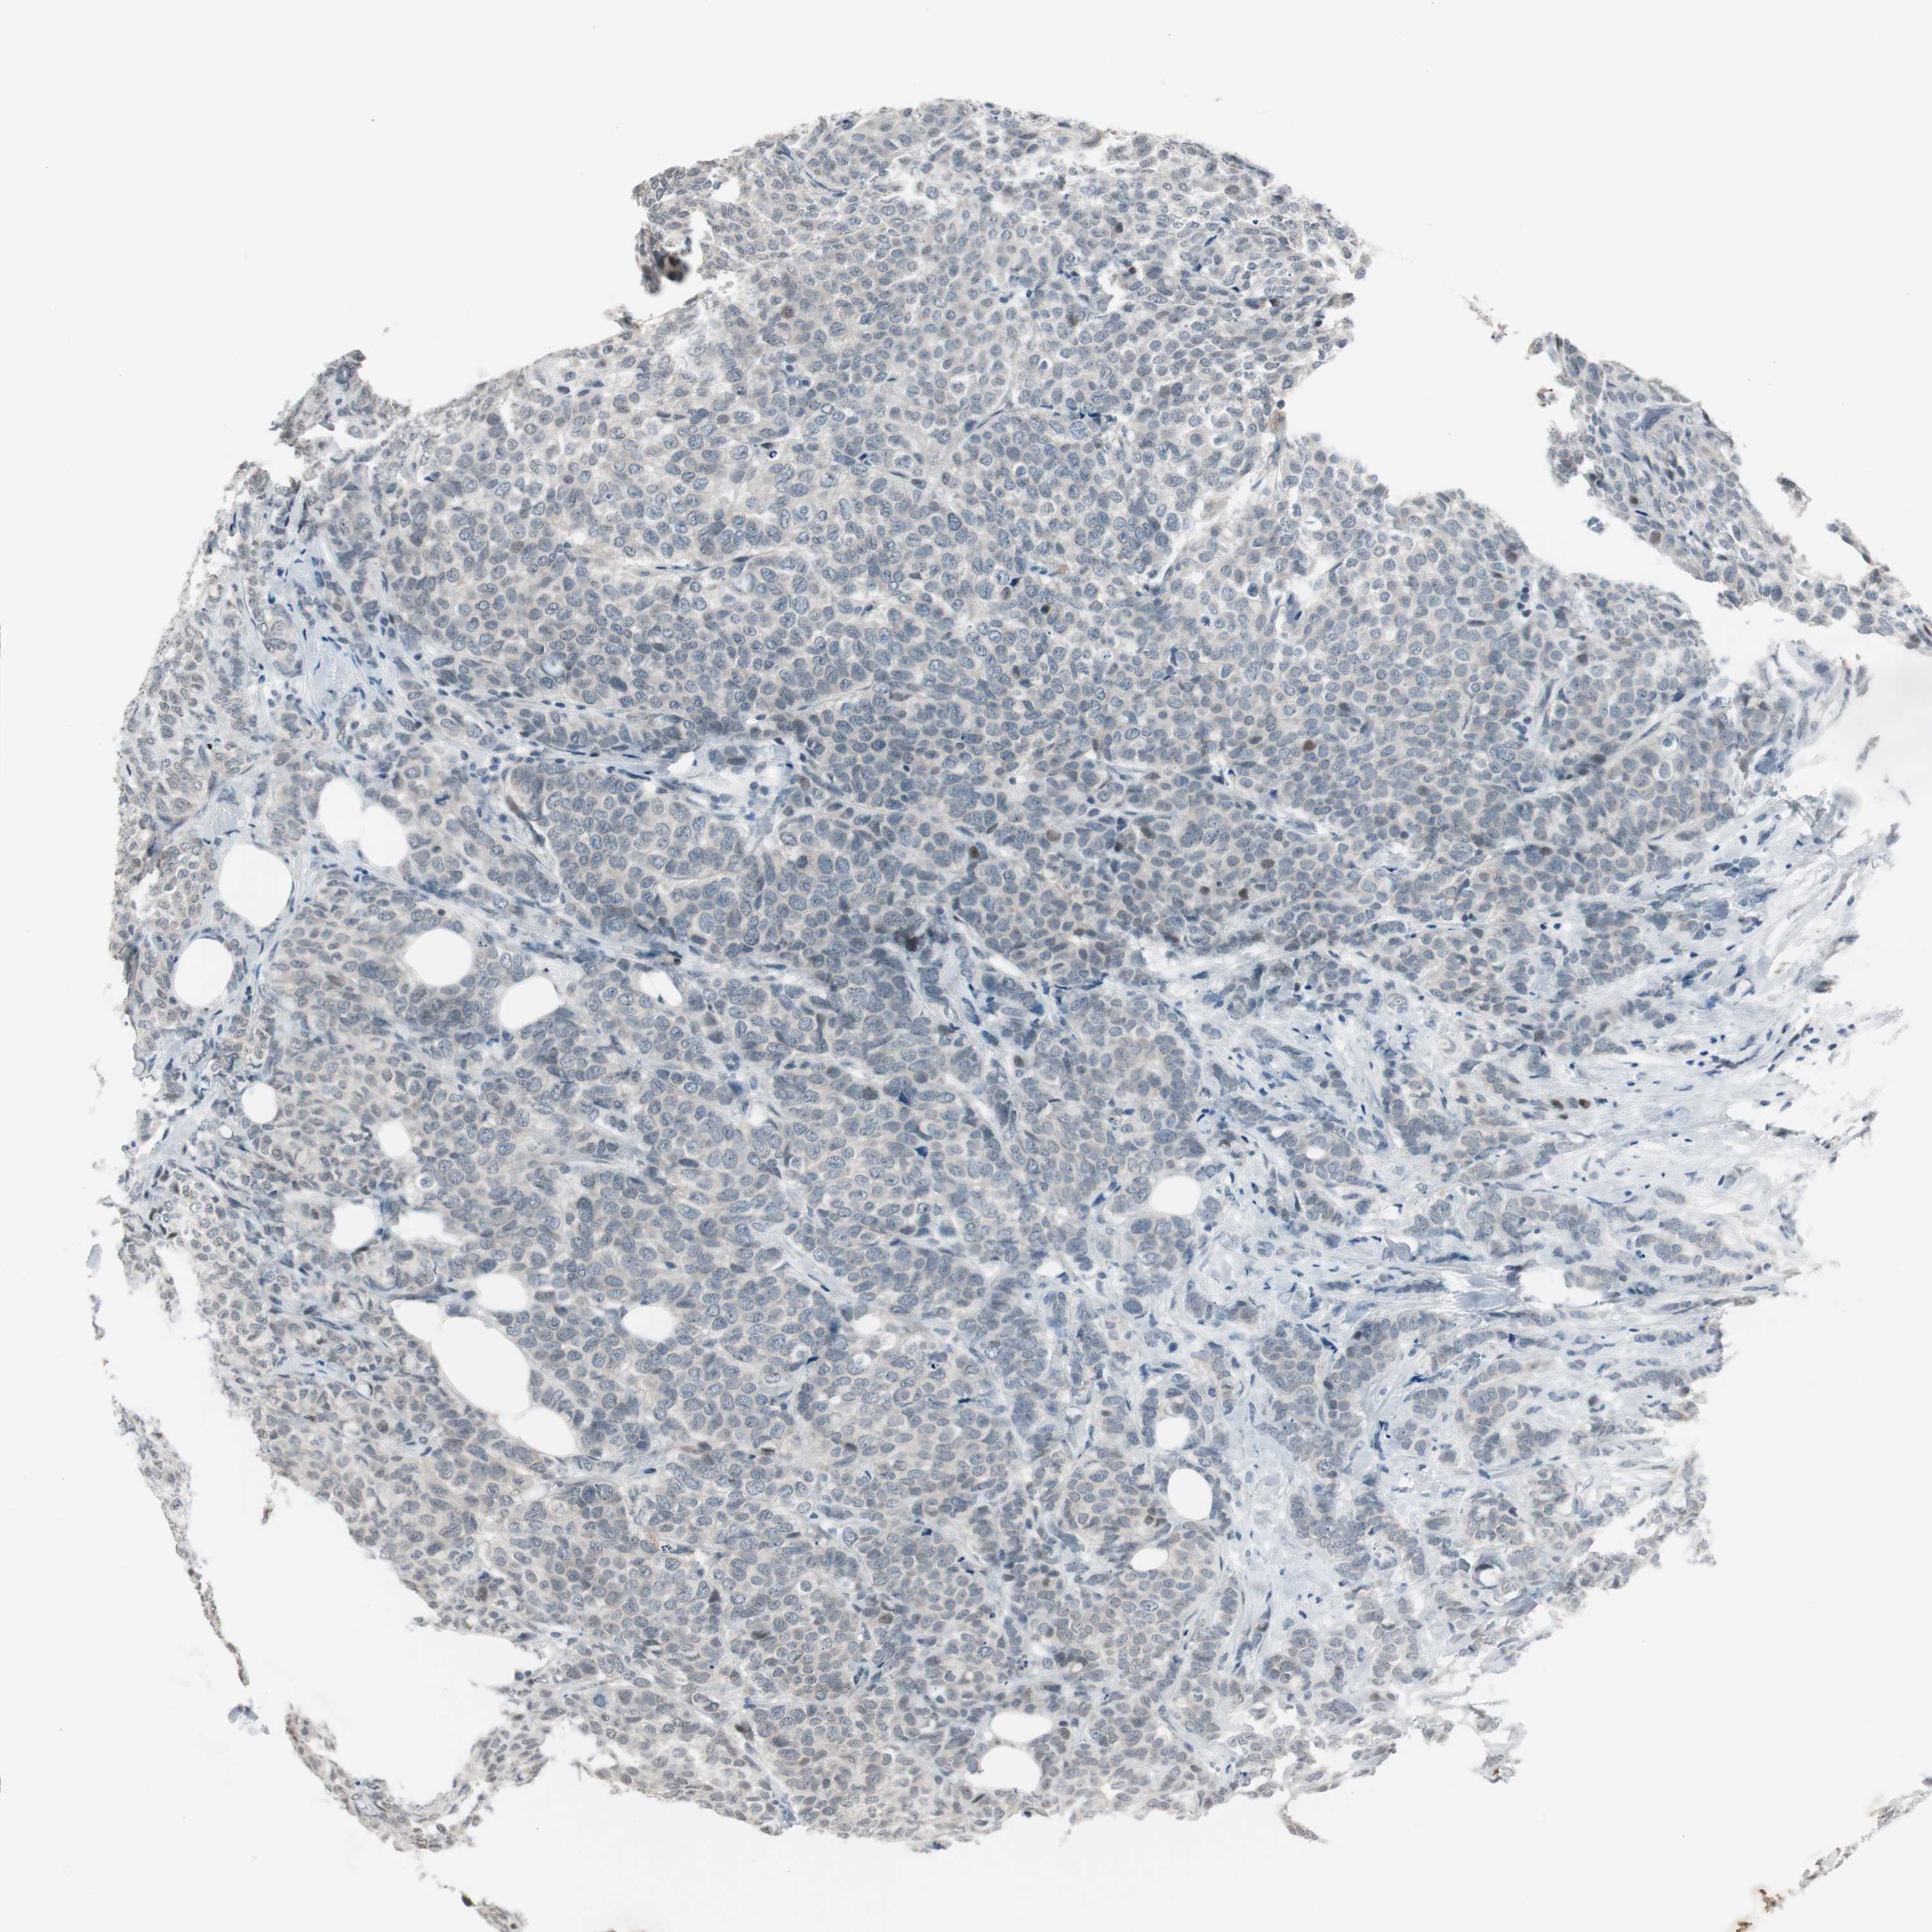

BRCA TCGA BRCA VALIDATION PROTEIN EXPRESSION